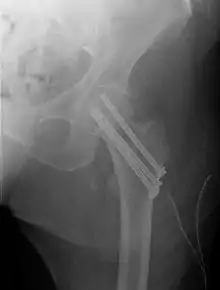

Fractures managed by closed reduction can possibly be treated by percutaneously inserted screws.[29]

Closed reduction may not be satisfactory and open reduction then becomes necessary.[32] The use of open reduction has been reported as 8-13% among pertrochanteric fractures, and 52% among intertrochanteric fractures.[33] Both intertrochanteric and pertrochanteric fractures may be treated by a dynamic hip screw and plate, or an intramedullary rod.[32]

Subtrochanteric fractures may be treated with an intramedullary nail or a screw-plate construction and may require traction pre-operatively, though this practice is uncommon. It is unclear if any specific type of nail results in different outcomes than any other type of nail.[34]